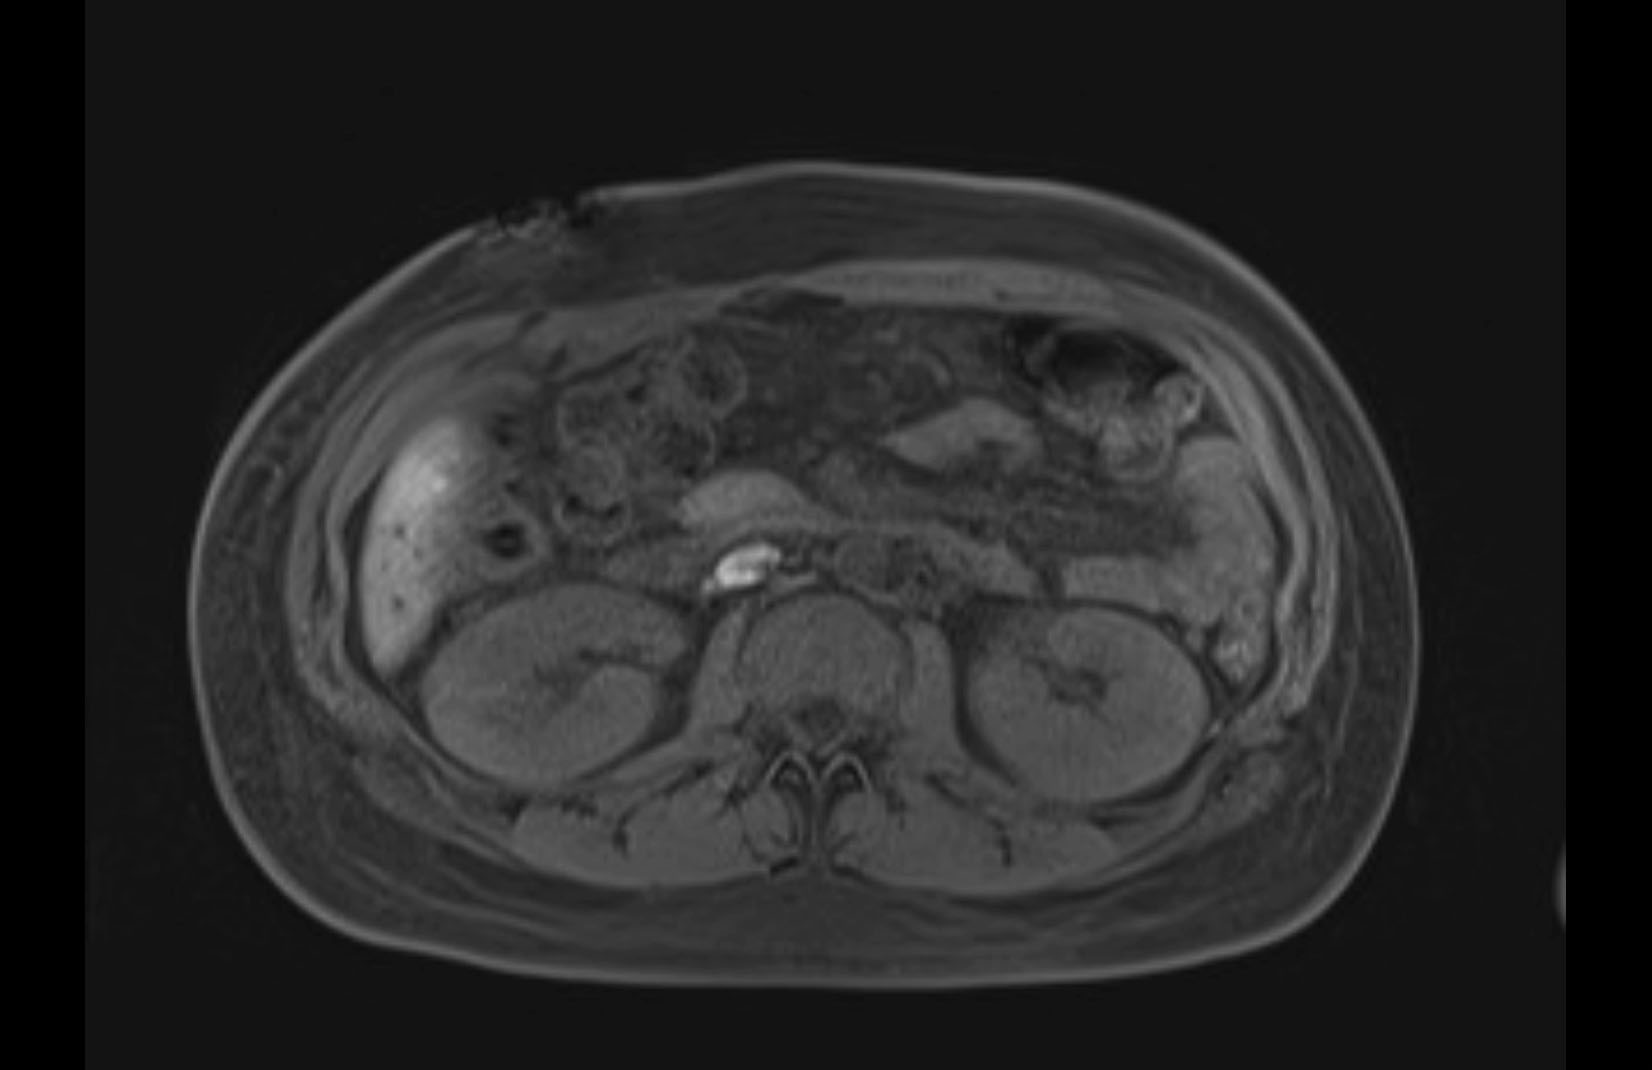

MRI T1

MRI T2